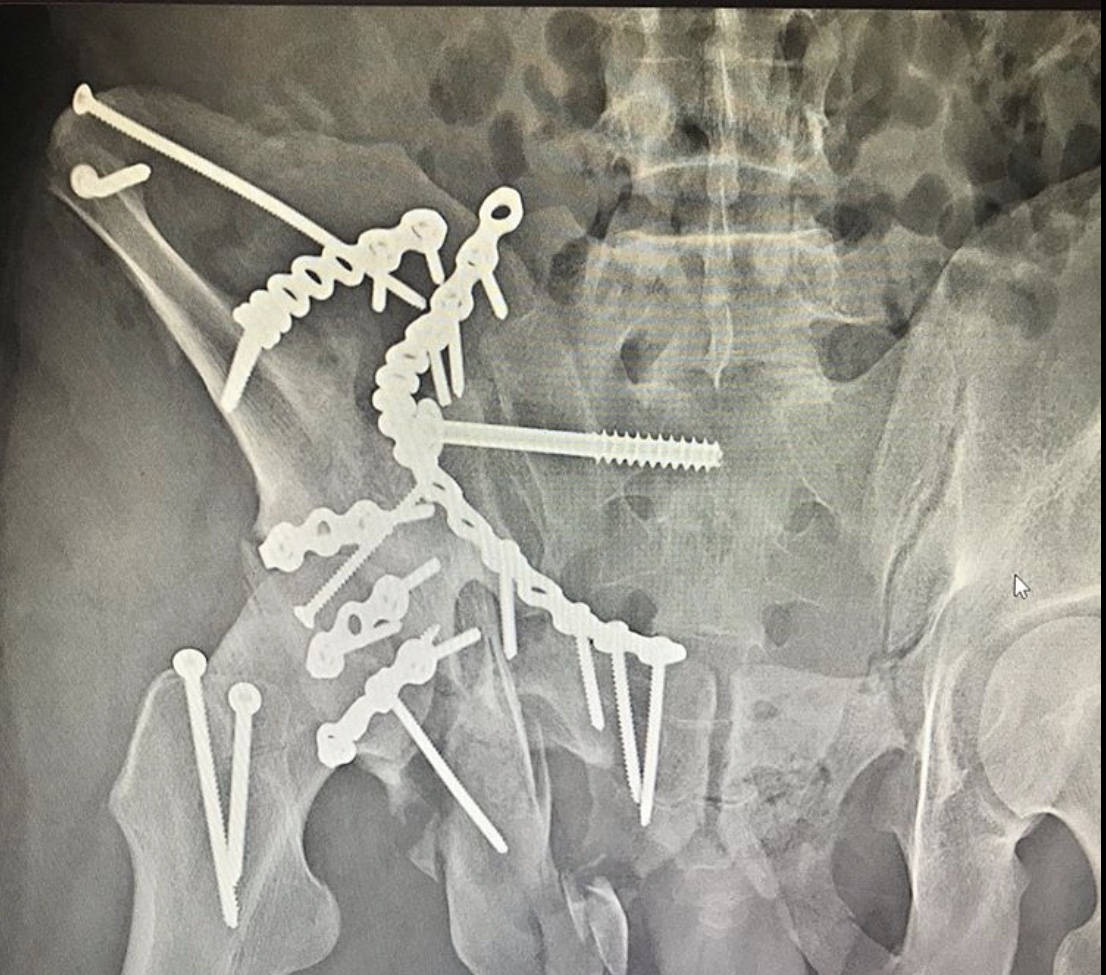

Пациента, что называется, «собрали».

Была выполнена открытая репозиция, остеосинтез пластинами.